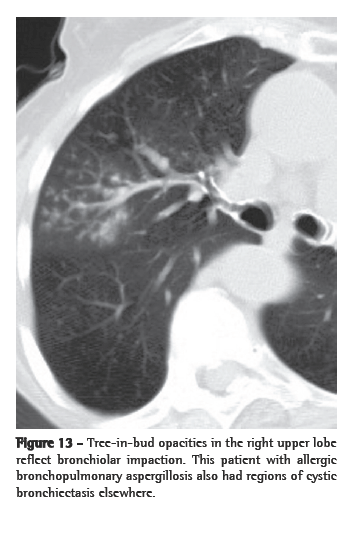

The central part of the secondary pulmonary lobule contains the branches of the terminal bronchioles, their accompanying pulmonary arteries, and, adjacent to them, supporting connective tissue with lymph vessels. Therefore, centrilobular nodular opacities can result from bronchiolar and peribronchiolar diseases, as well as from vascular and perivascular diseases. Mosaic attenuation associated with air trapping on expiratory HRCT, or functional evidence of airflow obstruction indicates diseases involving the peripheral airways. Centrilobular nodules are sometimes accompanied by the so-called "tree-in-bud" opacities, in which the abnormality resembles a budding tree. In the majority of cases, the tree-in-bud pattern occurs as a result of infectious diseases. Tree-in-bud is a subtype of a centrilobular pattern. Pathologically, this abnormality represents bronchiolar impaction and is almost always due to infection. The differential diagnosis is detailed in Chart 7.

In the immunocompromised host, bacterial (Staphylococcus aureus and

Haemophilus influenzae), fungal (more commonly Aspergillus spp.) and, quite rarely, viral infection can all result in a tree-in-bud pattern (Figure 13) accompanied by variable consolidation (including cytomegalovirus and respiratory syncytial virus).(55)